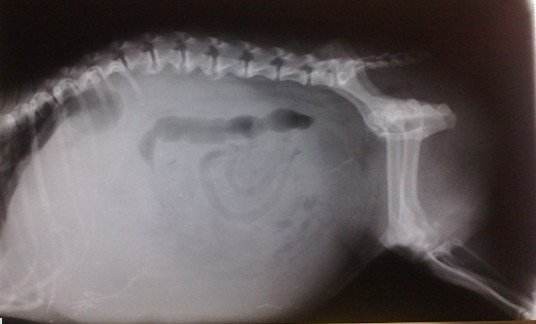

店长带了点力道揉了揉她的肚子,给她拍了个片,从内而外的检查个遍

宠物店店长猫咪很健康,你养的很好,看得出来你是个很好的主人。

宠物店店长你不用担心,她只是吃太多,有点积食

宠物店店长最近让她通通便就可以了